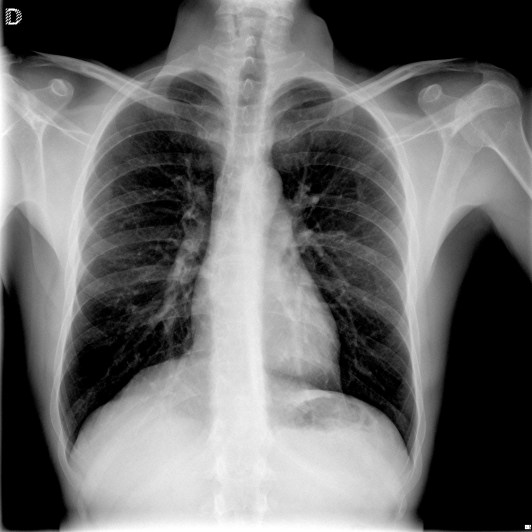

Solución: Es un estudio Normal. Silueta cardiomediastínica y parénquimas pulmonares sin alteraciones significativas.